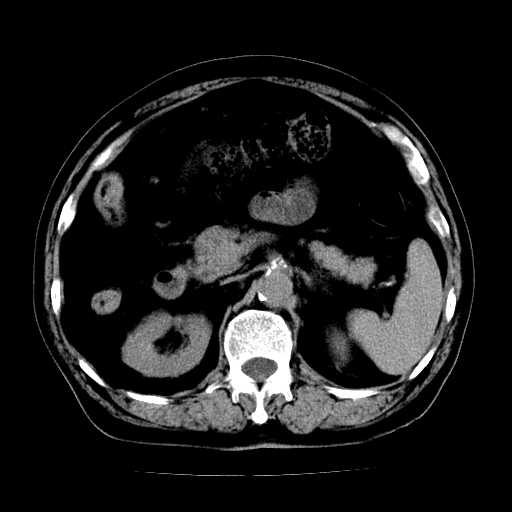

男,71岁,皮肤黄染四天。

肝内外胆管及胆总管上段扩张,考虑为梗阻所致,建议mrcp检查。

考虑胆总管癌并肝内外胆管扩张。

胰腺上端胆总管内见软组织影,强化不明显,结合临床,还是考虑低位梗阻性黄疸,胆总管癌可能性大